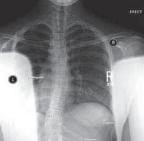

Chapter 59 Anterior Interbody Arthrodesis With Instrumentation for Scoliosis Daniel J. Sucato DEFINITION Thor…

Chapter 60 Thoracoscopic Release and Fusion for Scoliosis Daniel J. Sucato DEFINITION Thoracoscopy provides t…